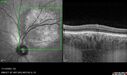

Central Retinal Vein Occlusion - Non-Ischemic - Excellent Outcome17 views57 year old man The right eye has had vision loss for about 3 weeks. He woke up with vision loss.

Medical Hx: HIV . Diabetes Mellitus (since 2014). Thyroid Disease.

Systemic Meds: gemboya. Metformin Hydrochloride. trulicity. losartan. vesepa. Synthroid .

VA OD: sc20/160 OS: sc20/20

TP: OD:14 OS:14

Treated with Avastin

VA 6 weeks later 20/32 – dry one shot.

Missed follow-up after second treatment and came 5 months later with good vision and no macular edemaAug 17, 2025